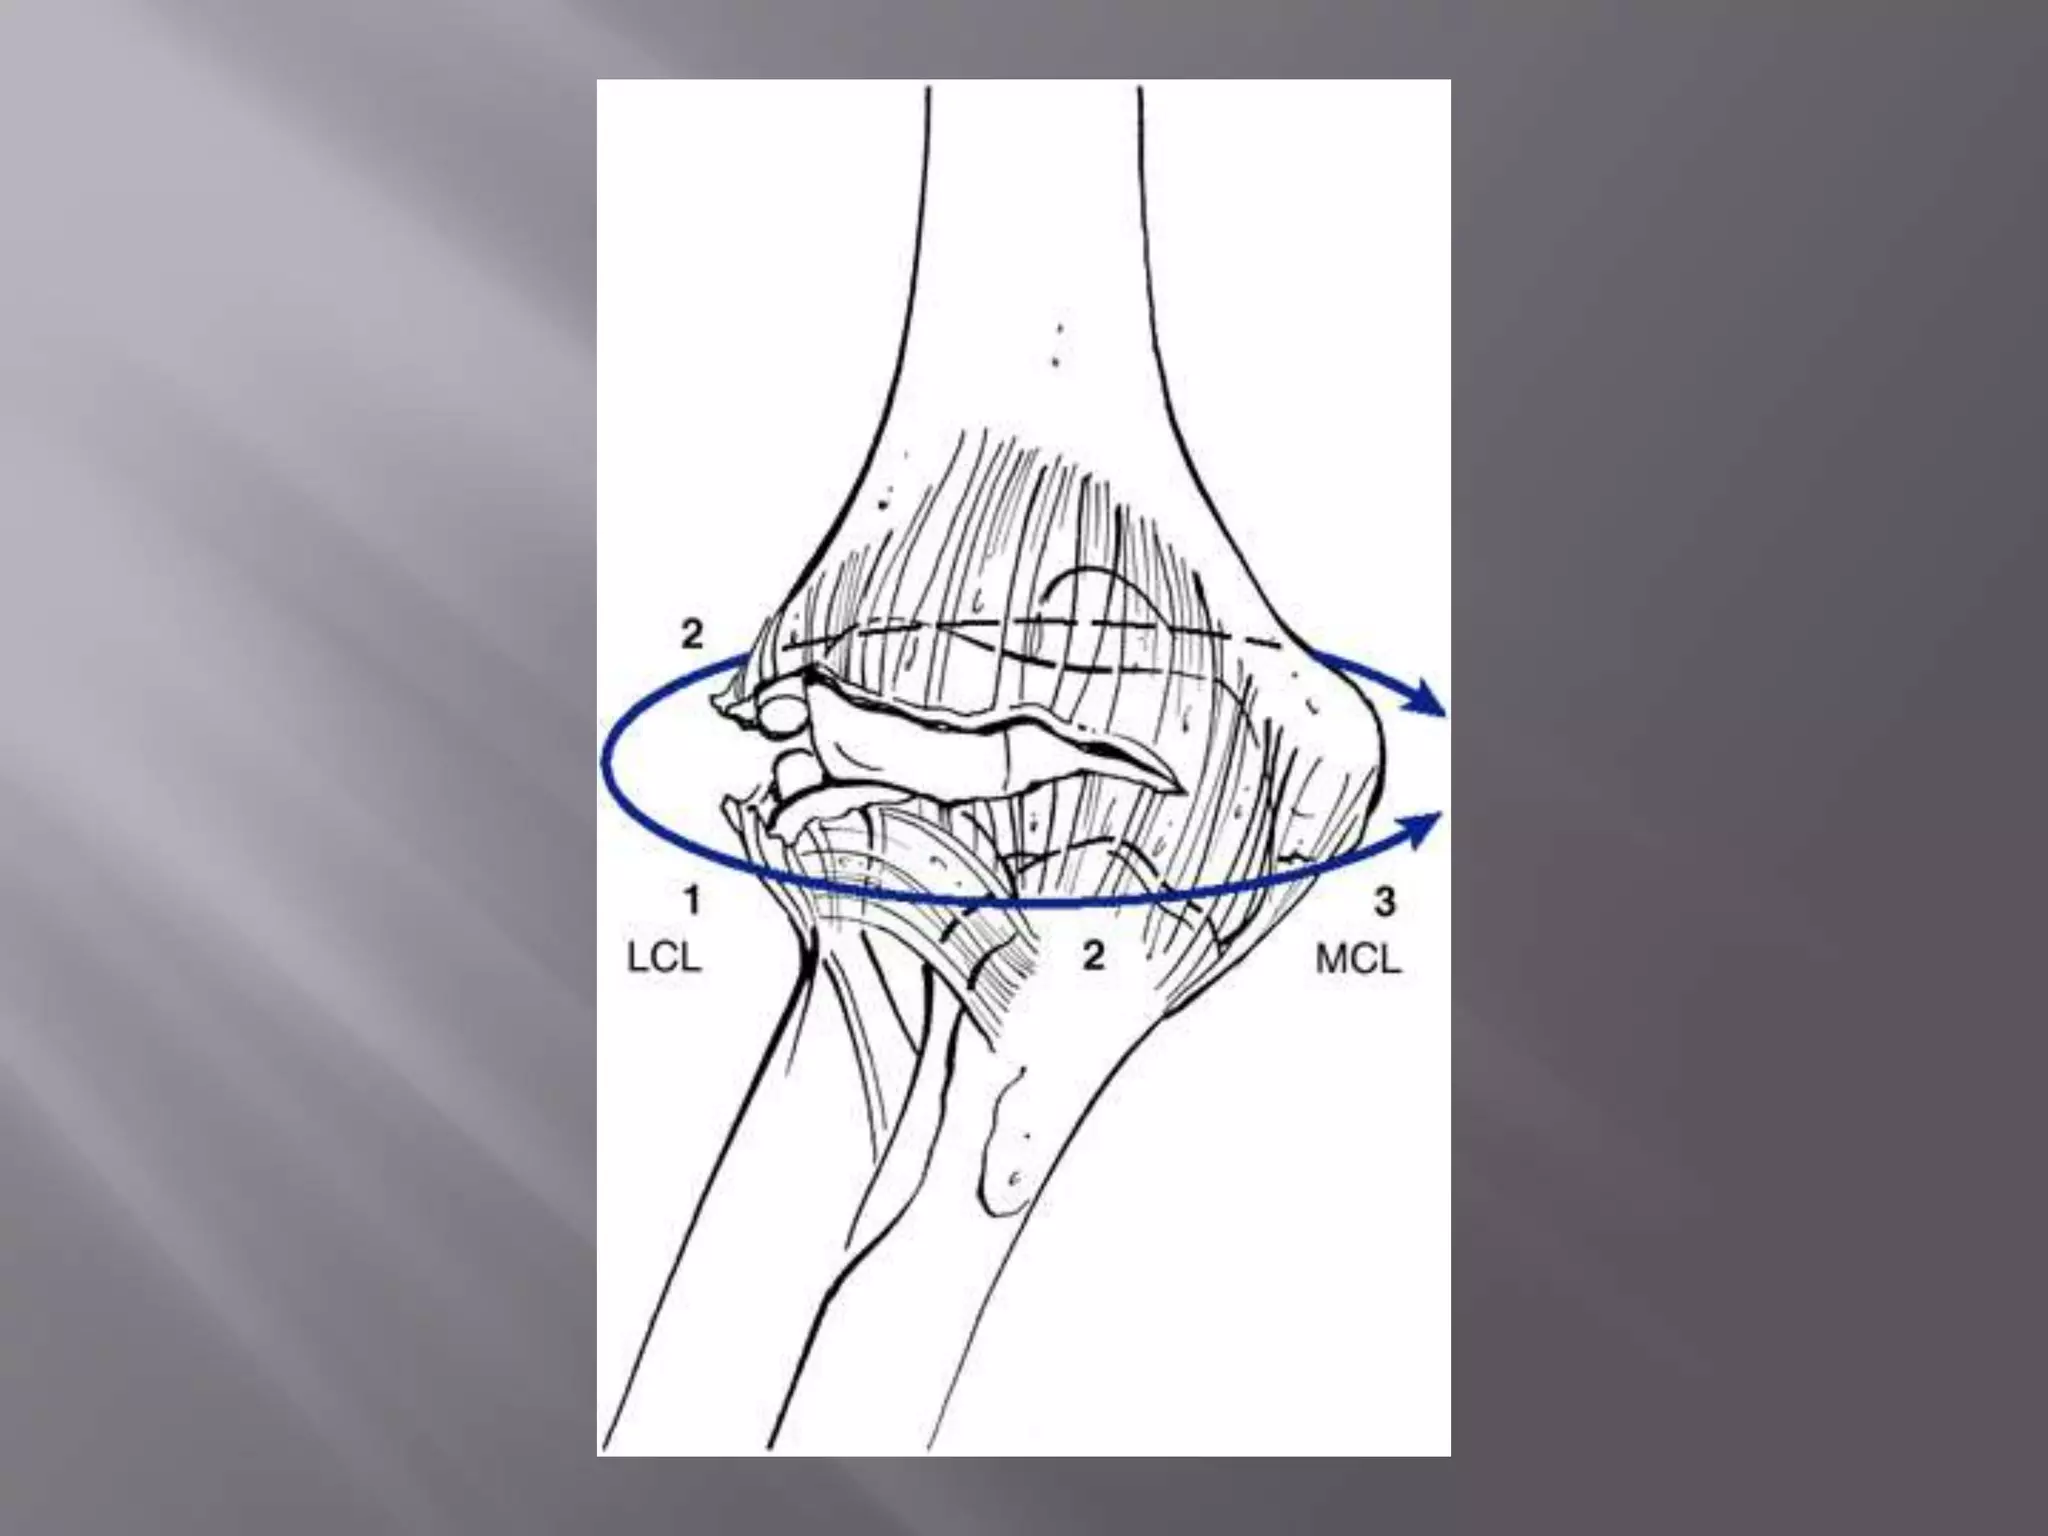

This document discusses the terrible triad injury of the elbow, which involves fractures of the radial head, coronoid process, and posterolateral dislocation. It notes the poor outcomes associated with this injury like stiffness, instability, and hardware failure. The document outlines the relevant anatomy of the medial collateral ligament and lateral uncular collateral ligament. It describes the mechanism of injury, known as the fall on an outstretched hand, and how the ligaments and capsule fail in this injury. Diagnostic imaging and classification of radial head and coronoid fractures are covered. Treatment options including observation, resection, open reduction internal fixation, and replacement are presented. Surgical approaches and techniques are also outlined.